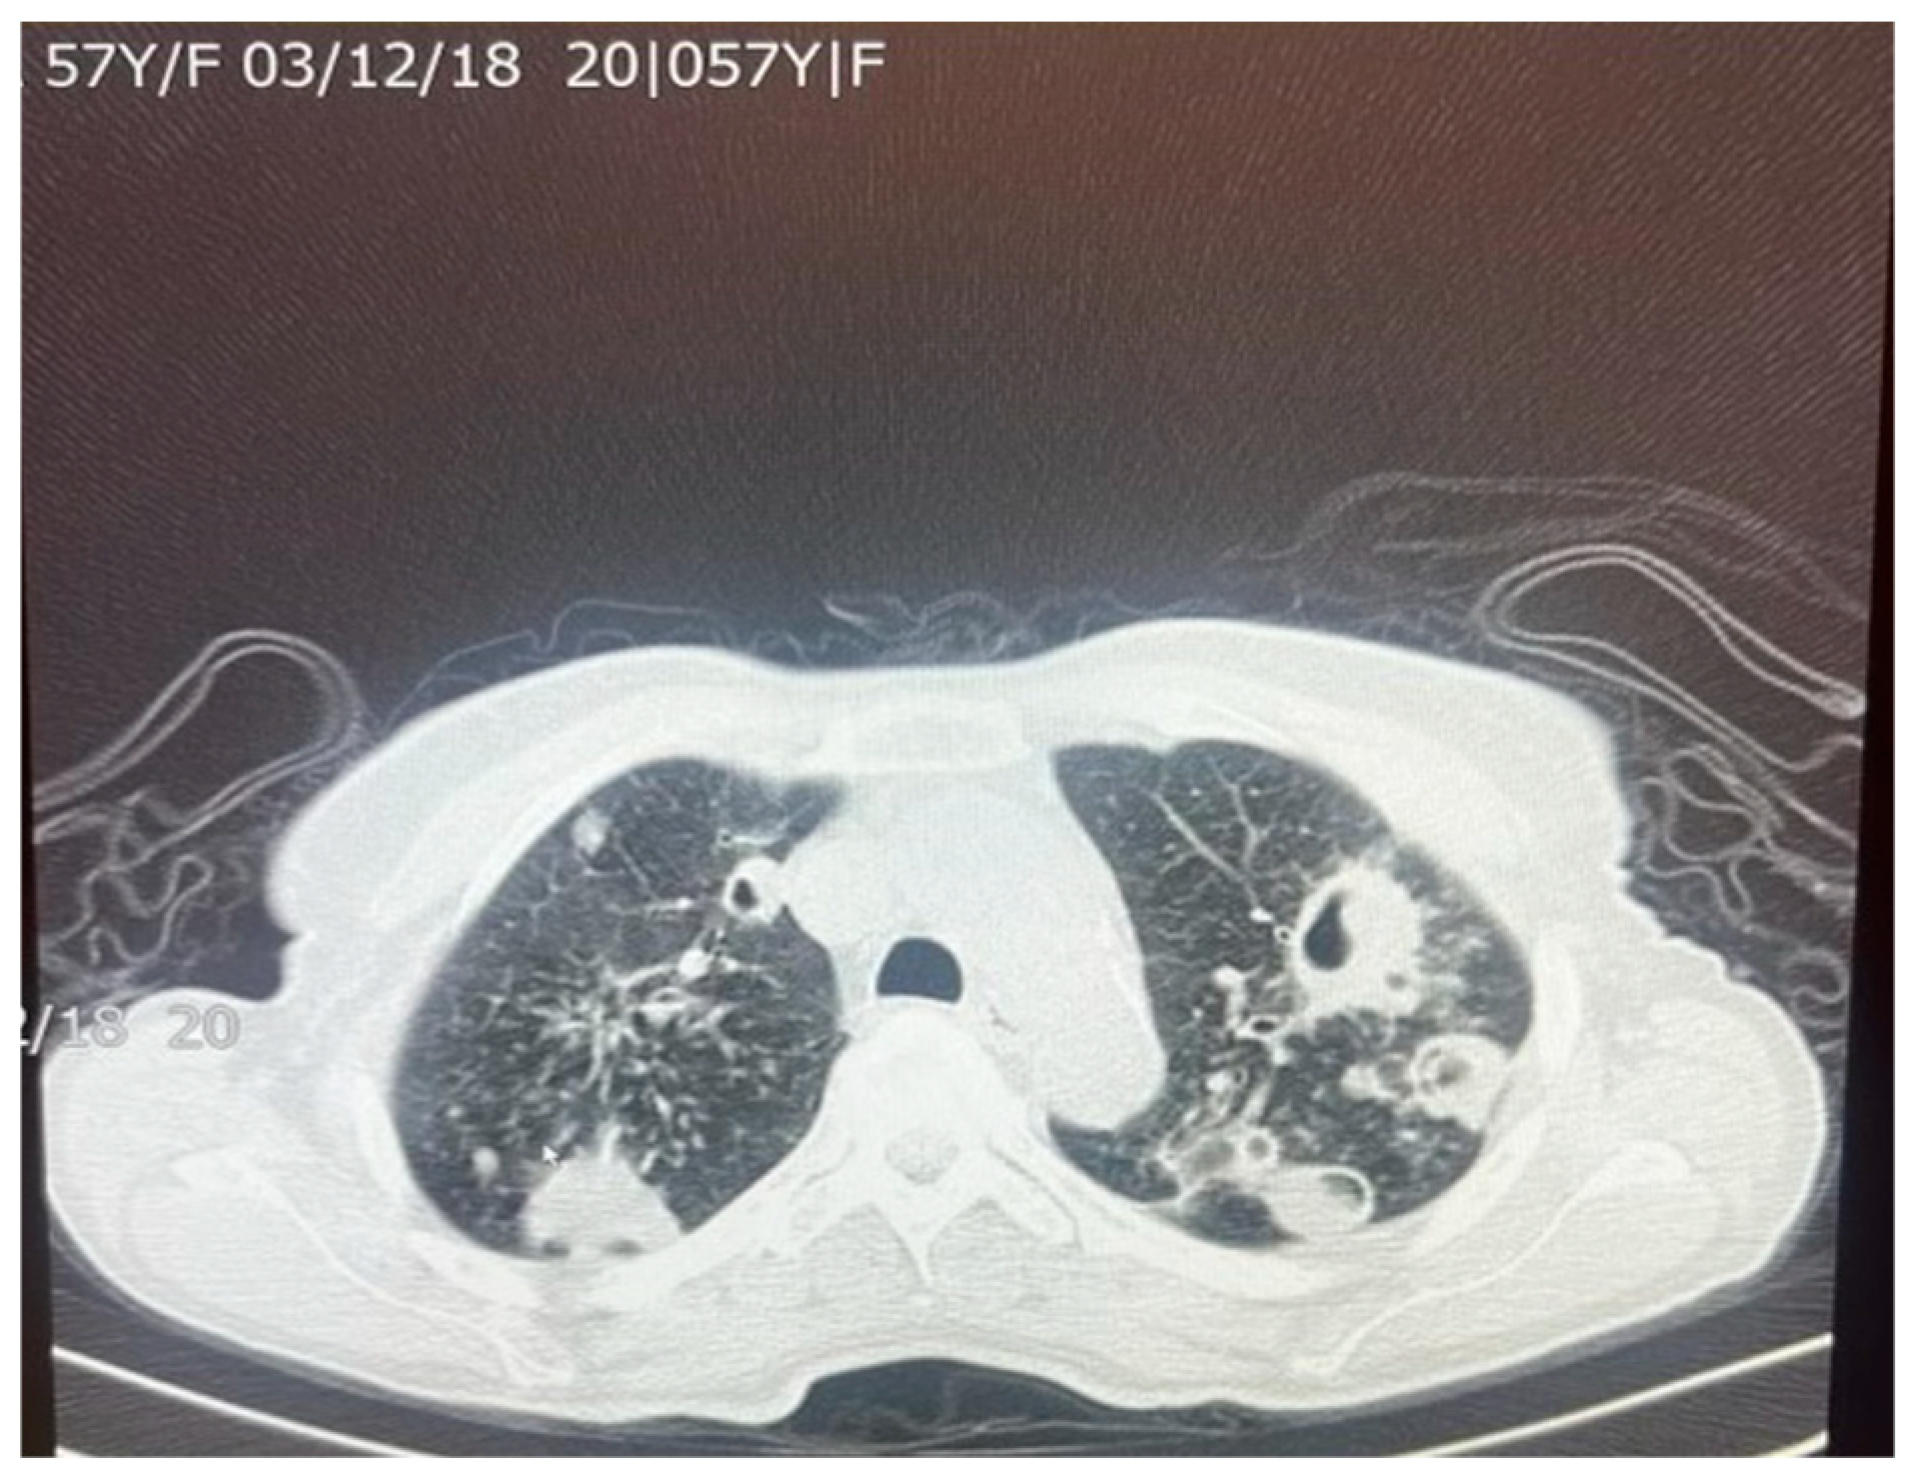

Figure 5. An axial chest CT scan of a 57-year-old female patient with pulmonary TB, showing bilateral pulmonary cavities and multiple nodules. The cavities are seen predominantly in the upper lobes, with irregular thickened walls, suggestive of active TB. The nodular lesions surrounding the cavities represent granulomatous inflammation, which is characteristic of TB infection. These findings are typical of post-primary TB in adults.

M. tuberculosis infection often leads to injury to the pleura. This includes the thickening and fibrosis of the pleura, and in many of these cases, patients further form calcification. About 40.9% of patients with fibrosis form these calcifications, as demonstrated in a CT-based study by Deshpande et al. [9]. The presence of fibrosis often results in decreased lung capacity on one side of the chest. This can be due to the cavities that form within the lungs as a result of the infection. In patients who had a single cavity in their lungs, fibrosis was found 100% of the time and calcification 80% of the time. In addition, 90% of these single cavities were found in the upper lobes of the lungs [9]. Upper lobe damage to the lungs can be seen in Figure 2. Further evidence of the presence of M. tuberculosis can be observed in Figure 3, in which many acid-fast bacilli are shown. The consistent presence of fibrosis and calcification in these cases suggests prolonged infection. This represents the host’s attempt to contain the mycobacterial focus. Fibrosis may contribute to disrupted lung structure and functional impairment of the lung, while calcification often marks the healing or inactive phase of a granulomatous lesion.

A total of 83–85% of M. tuberculosis infections tend to infect the apical or posterior areas of the upper lobes, likely due to the high levels of oxygen compared to the lower lobes. The higher concentration of oxygen allows for greater multiplication of the bacterium. Fibrosis of the lung tissue begins once the healing process starts. The resulting fibrosis and granulomas both impede normal airflow in the lungs. Difficulty in breathing is further exacerbated by the buildup of large levels of mucus. As the body tries to heal the tissue, calcium forms as a sequelae of chronic inflammation. Calcification from lymph nodes continues to increase, forming calcification of the bronchial tree, causing coughing and wheezing to worsen [10]. Although this process of broncholithiasis is uncommon, it highlights the potential downstream effects of chronic calcification.

M. tuberculosis can alter the normal lung architecture in cases of both latent and active disease and even cause permanent damage after resolution of the infection. Damage to lung tissue, such as the replacement of tissue with scar tissue, can permanently alter respiratory function, leading to significant morbidity well after the bacterium has been cleared. Figure 5 and Figure 6 illustrate the pattern of damage that points to the reactivation of TB. The cyclical process of tissue injury, immune-mediated inflammation, and healing contributes to fibrosis and calcification, which may lead to both obstructive and restrictive patterns of lung disease. Obstructive dysfunction can result from airway inflammation, loss of elastic recoil, and post-infectious bronchiectasis—the latter characterized by permanent dilation of the bronchi. On the other hand, restrictive changes arise from exaggerated immune responses and chronic inflammation, leading to fibrosis and stiffening of the lung parenchyma. The degree of respiratory mechanic abnormalities (i.e., pulmonary function tests) from M. tuberculosis infection can vary depending on multiple factors such as patient age, geographic location, or the drug resistance of the bacteria [25].